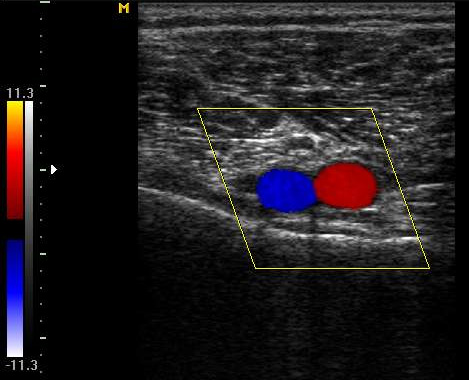

Цветная картинка является более наглядной и удобной в использовании: направление тока крови определяется и выделяется синим или красным цветом, а оттенок свидетельствует о скорости течения в данном сосуде.

Триплексное сканирование это распространенное называние сочетания дуплексной допплерометрии с цветовым картированием.

Проксимальную компрессию считают причиной расширения берцовых вен в 1,5-2 раза. В таких случаях клапаны приобретают четкий характер. Если просвет сосуда показывается при цветовом кодировании как эхонегативный, значит, в нем отсутствует ретроградный кровоток.

Если просвет окрашен в синий цвет, а допплеровский шум усилился, это является признаком выраженного антеградного кровотока (результата декомпрессии).

Диагностика варикоза

Дистальная компрессия характеризуется синим цветом кровотока на мониторе и усилением сигнала допплерографа. Если устранить компрессию, то просвет сосуда станет эхонегативным, а сигнал почти исчезнет.